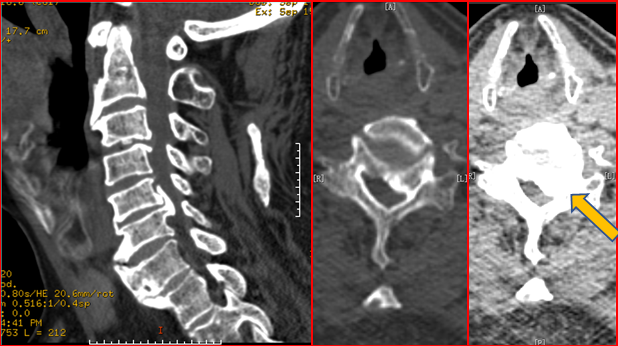

颈椎CT示:C6水平椎管内占位

诊断:脊膜瘤

手术治疗方案:显微镜辅助下颈椎后路减压内固定术